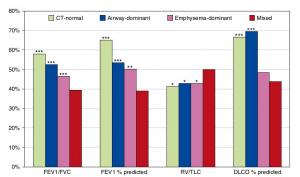

A Mixed Phenotype of Airway Wall Thickening and Emphysema Is Associated with Dyspnea and Hospitalization for Chronic Obstructive Pulmonary Disease.

Radiological Approach to Asthma and COPD-The Role of Computed Tomography.